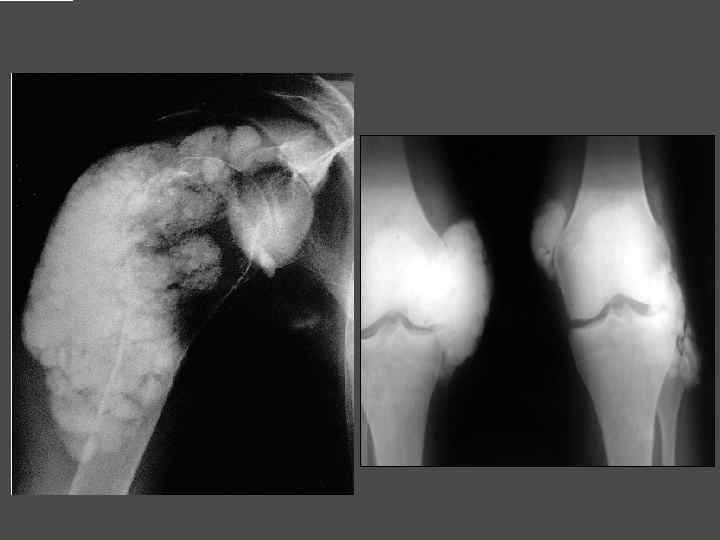

КЛИНИЧЕСКАЯ КАРТИНА ► Мышечная слабость ► Быстрая утомляемость ► Выпадение зубов ► Боли в суставах ► Резорбция костной ткани → патологические переломы ► Деформация лицевого скелета ► Мочекаменная болезнь ► Язвенная болезнь ► Кожный зуд ► Формирование патологических оссификатов в мягких тканях

Метастатическая кальцификация мягких тканей, околосуставной кальциноз